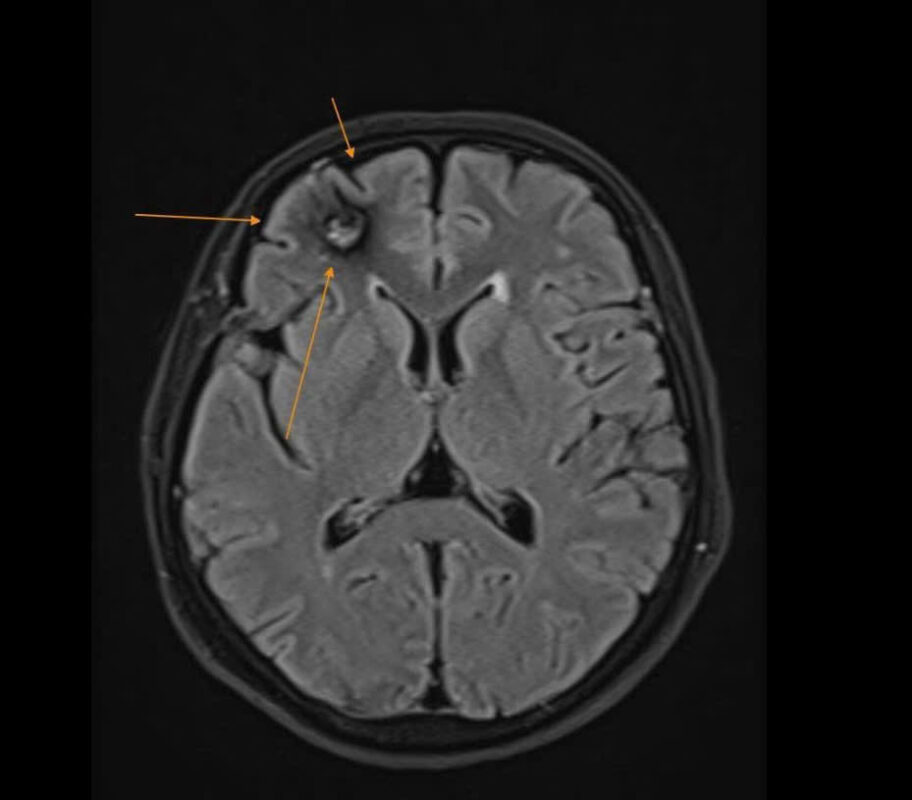

Trước đó, người bệnh đã chụp cắt lớp vi tính (CT scanner) sọ não tại một cơ sở y tế khác nhưng không phát hiện bất thường. Sau khi thăm khám, bệnh nhân được bác sĩ tư vấn chụp cộng hưởng từ sọ não (MRI 1.5 Tesla) tại Bệnh viện Đa khoa Quang Thành, kết quả cho thấy:

U máu thể hang (Cavernoma) có biến chứng xuất huyết giai đoạn bán cấp.

Tổn thương này có nguy cơ gây co giật hoặc tái xuất huyết; nếu không được phát hiện và theo dõi sớm có thể để lại hậu quả nặng nề.